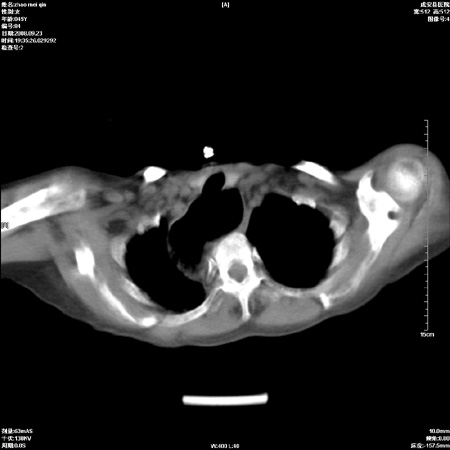

标题: CT15861:女 60 外伤后1小时 胸疼 [打印本页]

标题: CT15861:女 60 外伤后1小时 胸疼

外伤后1小时 胸疼 是外伤后引起的吗?

食道扩张明显下端逐渐变窄,倒像贲门失迟缓

非外伤性改变,典型的贲门失迟缓症

食道扩张明显下端逐渐变窄,大量食物存留,象贲门失迟缓症。